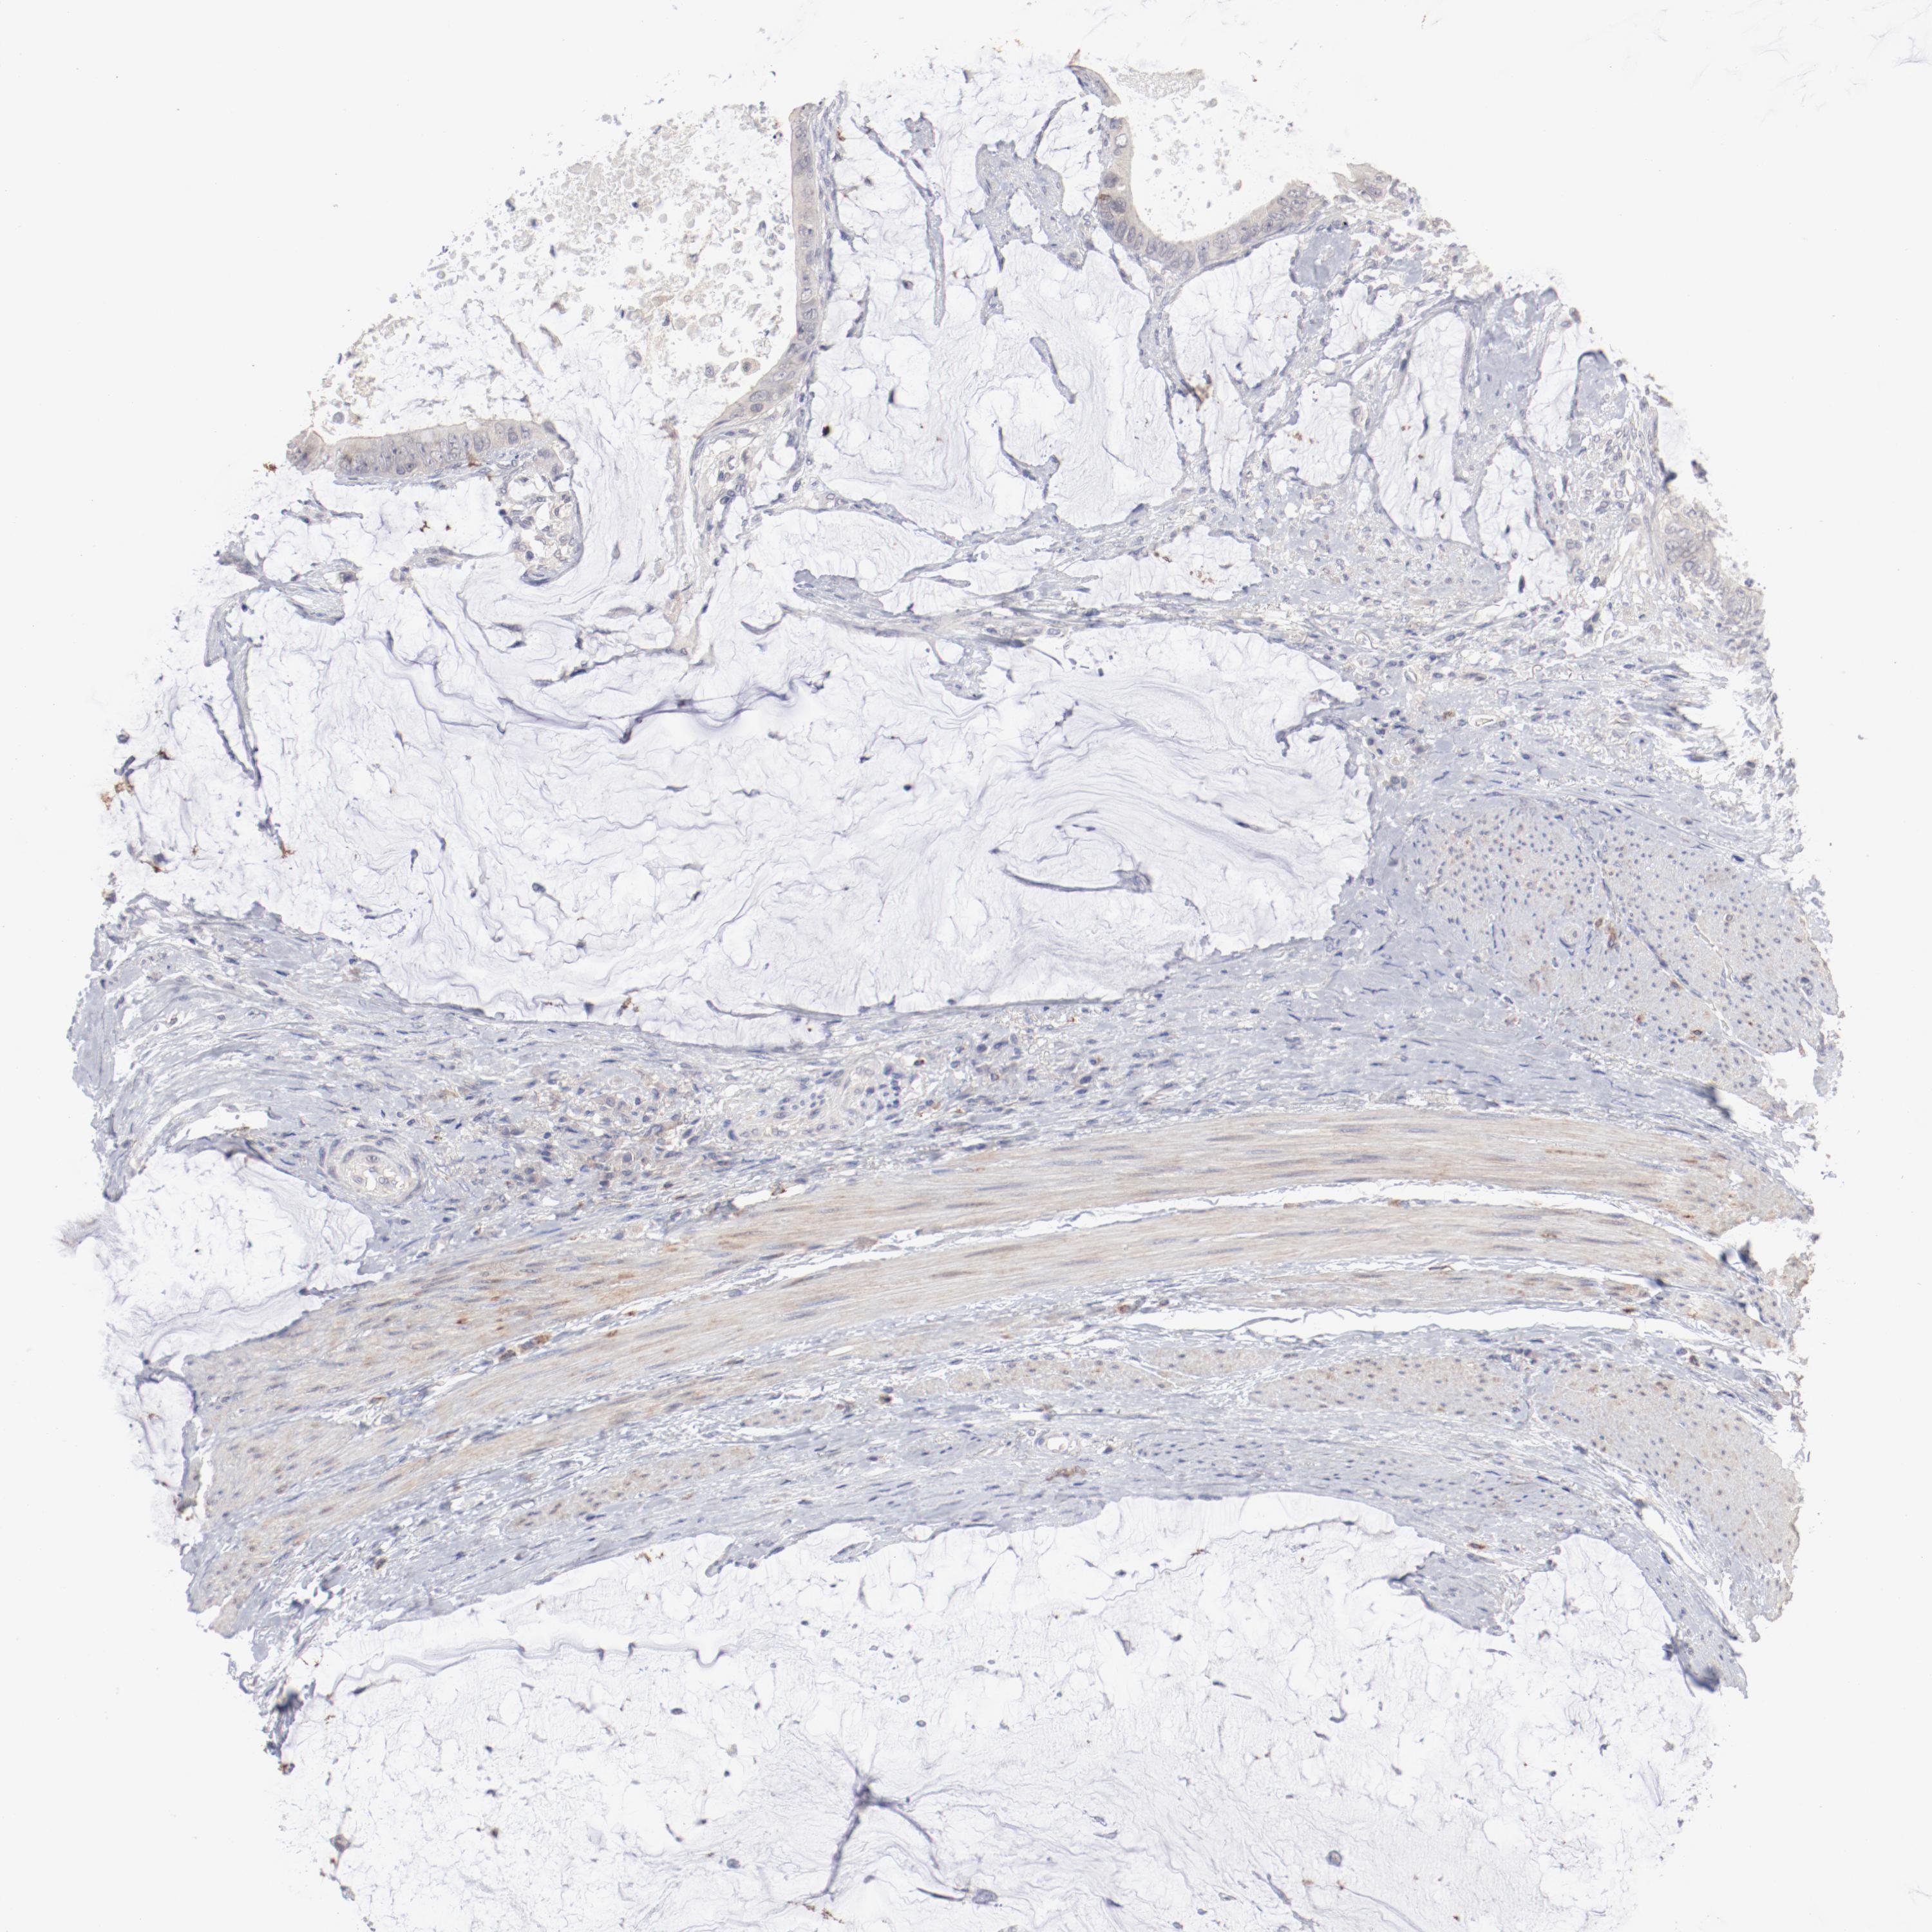

ANTIBODIES

AND

VALIDATION

Dictionary

Colorectal cancer

Human cancer